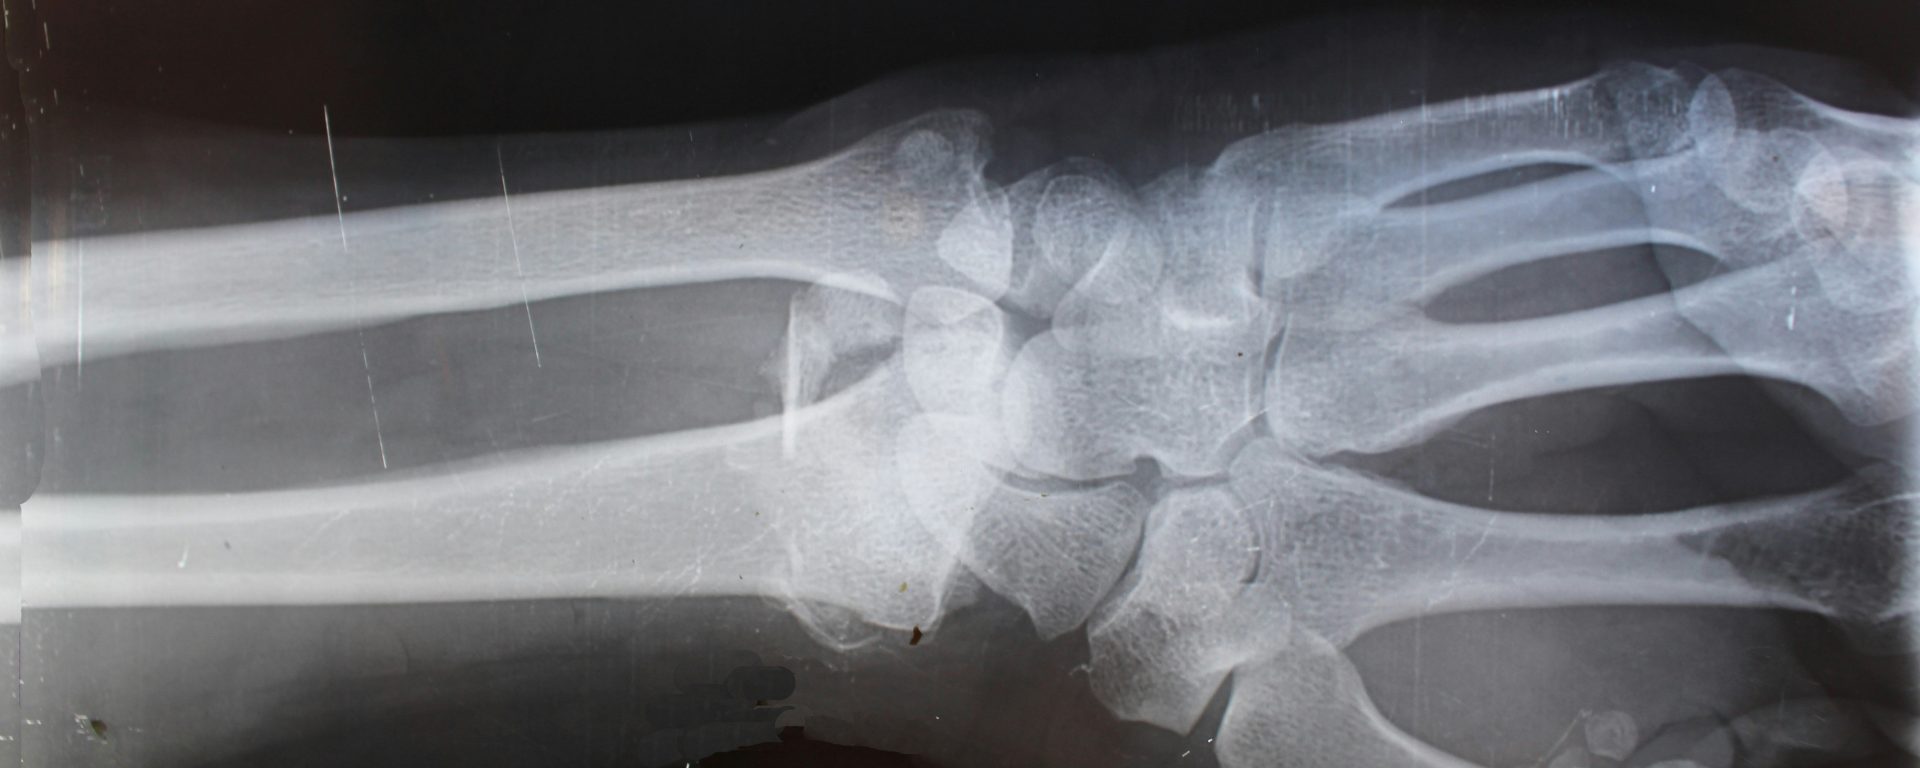

Radiologic technologists are primarily responsible for setting up and operating specialized imaging equipment, including X-ray technology, magnetic resonance imaging (MRI) scanners, and computed tomography (CT) machines. Radiologic technologists use these to create images of patients’ bodies (or areas of concern), which are then used to diagnose and treat conditions.

- Conduct medical imaging using advanced equipment like MRIs, CT machines, ultrasounds, fluoroscopy equipment, and more

- Interpret images in collaboration with medical team, helping providers to identify abnormalities and produce/develop reports